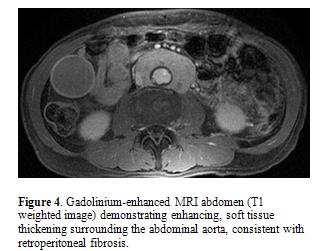

The most common site of extra-pancreatic involvement is the biliary tree presenting with asymptomatic liver test abnormalities or jaundice (23). On imaging, biliary involvement commonly appears as multifocal biliary strictures similar to primary sclerosing cholangitis. On CT or MR, the strictured bile duct commonly appears as diffuse or focal thickening of the wall. Rarely, it may form a mass which mimics cholangiocarcinoma. The kidneys are also commonly involved (25). On CT or MR, renal lesions are commonly bilateral and multiple, predominantly involving renal cortex (Figure 3). Renal parenchymal lesions can be classified as small peripheral cortical nodules, round or wedge-shaped lesions, and diffuse patchy involvement. Renal lesions may present as a large solitary mass which mimics primary renal neoplasm. Retroperitoneal fibrosis is seen in 10% of cases (Figure 4).

A recent study by Deshpande et al (4) showed that pancreatic tail cut-off sign was only seen in type 2 AIP (4/10). Other imaging features such as the type of pancreatic swelling, presence of capsule-like rim, and common bile duct strictures were not helpful in distinguishing the two types. An international multicenter survey showed that diffuse swelling of pancreas was more common in type 1 compared to type 2 AIP (40% vs 25%) (10). The pattern of extrapancreatic organ involvement is distinct between the two types and helpful when present (10). Biliary or renal involvement and retroperitoneal fibrosis are exclusively seen in type 1 AIP, whereas inflammatory bowel disease is commonly associated with type 2 AIP (10).

Imaging features of CT and MR are critical for establishing the diagnosis of AIP and excluding other potential etiologies, particularly pancreatic cancer. Classic imaging features which are relatively specific for AIP include diffuse pancreatic enlargement, presence of a hypoattenuating capsule rim, and delayed parenchymal enhancement. Although not always present, findings of multifocal narrowing of the main pancreatic duct or other organ involvement such as biliary strictures, renal involvement, and retroperitoneal fibrosis are helpful clues for AIP diagnosis. The imaging variants of AIP (focal and multifocal involvement) are sometimes indistinguishable from malignancy and require careful evaluation for collateral diagnostic evidence.